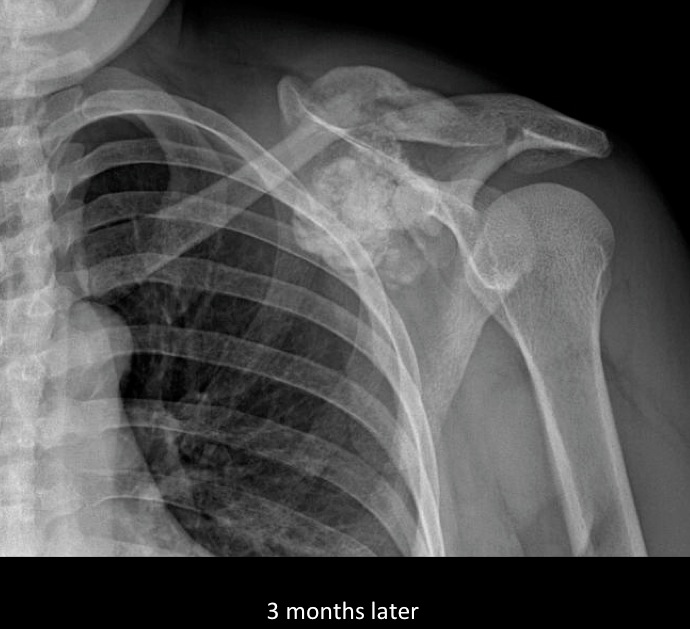

Figure 2 for case Presumed brown tumor and tumoral calcinosis

Figure 2